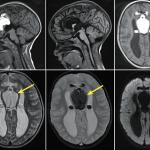

Tachycardie atriale focale

Un homme de 26 ans, militaire, consulte dans le cadre de sa visite de contrôle périodique d’aptitude au parachutisme...